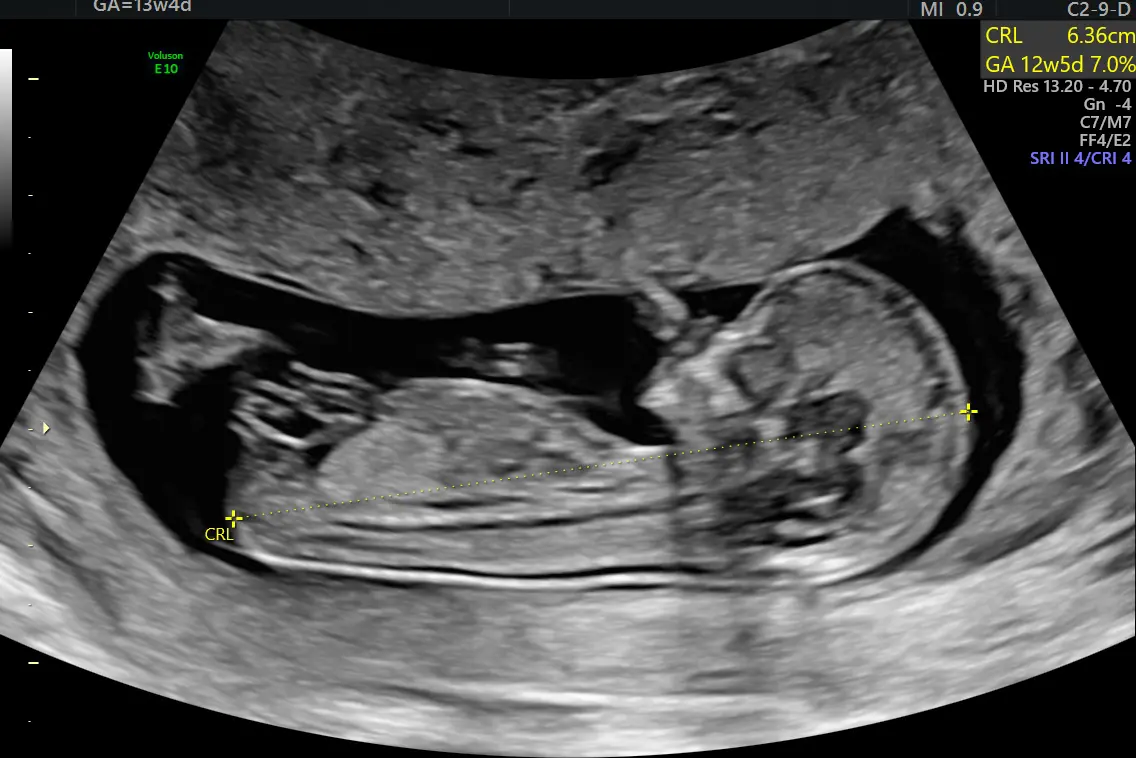

Ultrabildet av foster er godkjent av foreldre. Foto: OUS Rikshospitalet.

I tillegg kan vi undersøke fosterets organer. Men husk at fosteret i første trimester er lite med hode-sete lengde 4,5-8,5 cm, se bildet ovenfor.

Samtidig kan vi se etter ultralydmarkører for kromosomfeil, som for eksempel fortykket nakke. Kromosomavvik oppstår ganske ofte, men de fleste fostre med kromosomsykdom blir spontant abortert før uke 12.

Ved hjelp av ultralyd kan vi beregne hvor stor sjanse fosteret har for å ha kromosomavvik. En bedre og mer presis metode for å estimere denne risikoen er å undersøke det føtale arvestoffet (DNA) som sirkulerer i mors blod allerede i uke 10, såkalt NIPT.